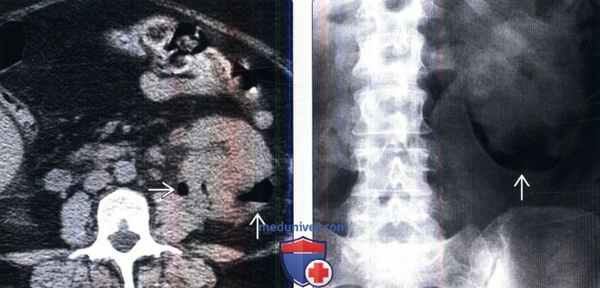

(Слева) КТ без контрастирования, аксиальная проекция: у женщины 69 лет с сахарным диабетом, поступившей с лихорадкой и болью в боку, выявлены крупные скопления газа и жидкости в паренхиме почки слева. Такая картина характерна для абсцесса, продуцирующего газ, сформировавшегося вследствие наличия эмфизематозного пиелонефрита.

(Справа) Рентгенография в переднезадней проекции: у этой же пациентки имеется нелинейное скопление газа , очерчивающее нижний полюс левой почки.